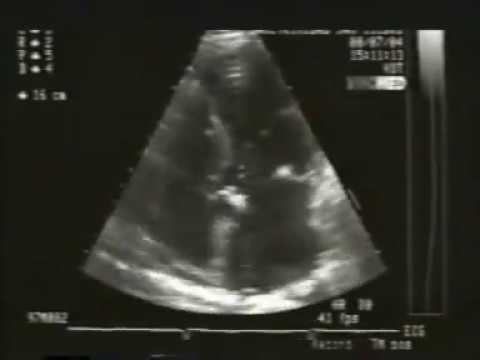

Una ecocardiografía es un examen que emplea ondas sonoras para crear una imagen en movimiento del corazón. Es mucho más detallada que una radiografía normal, y además no implica exposición a radiación.